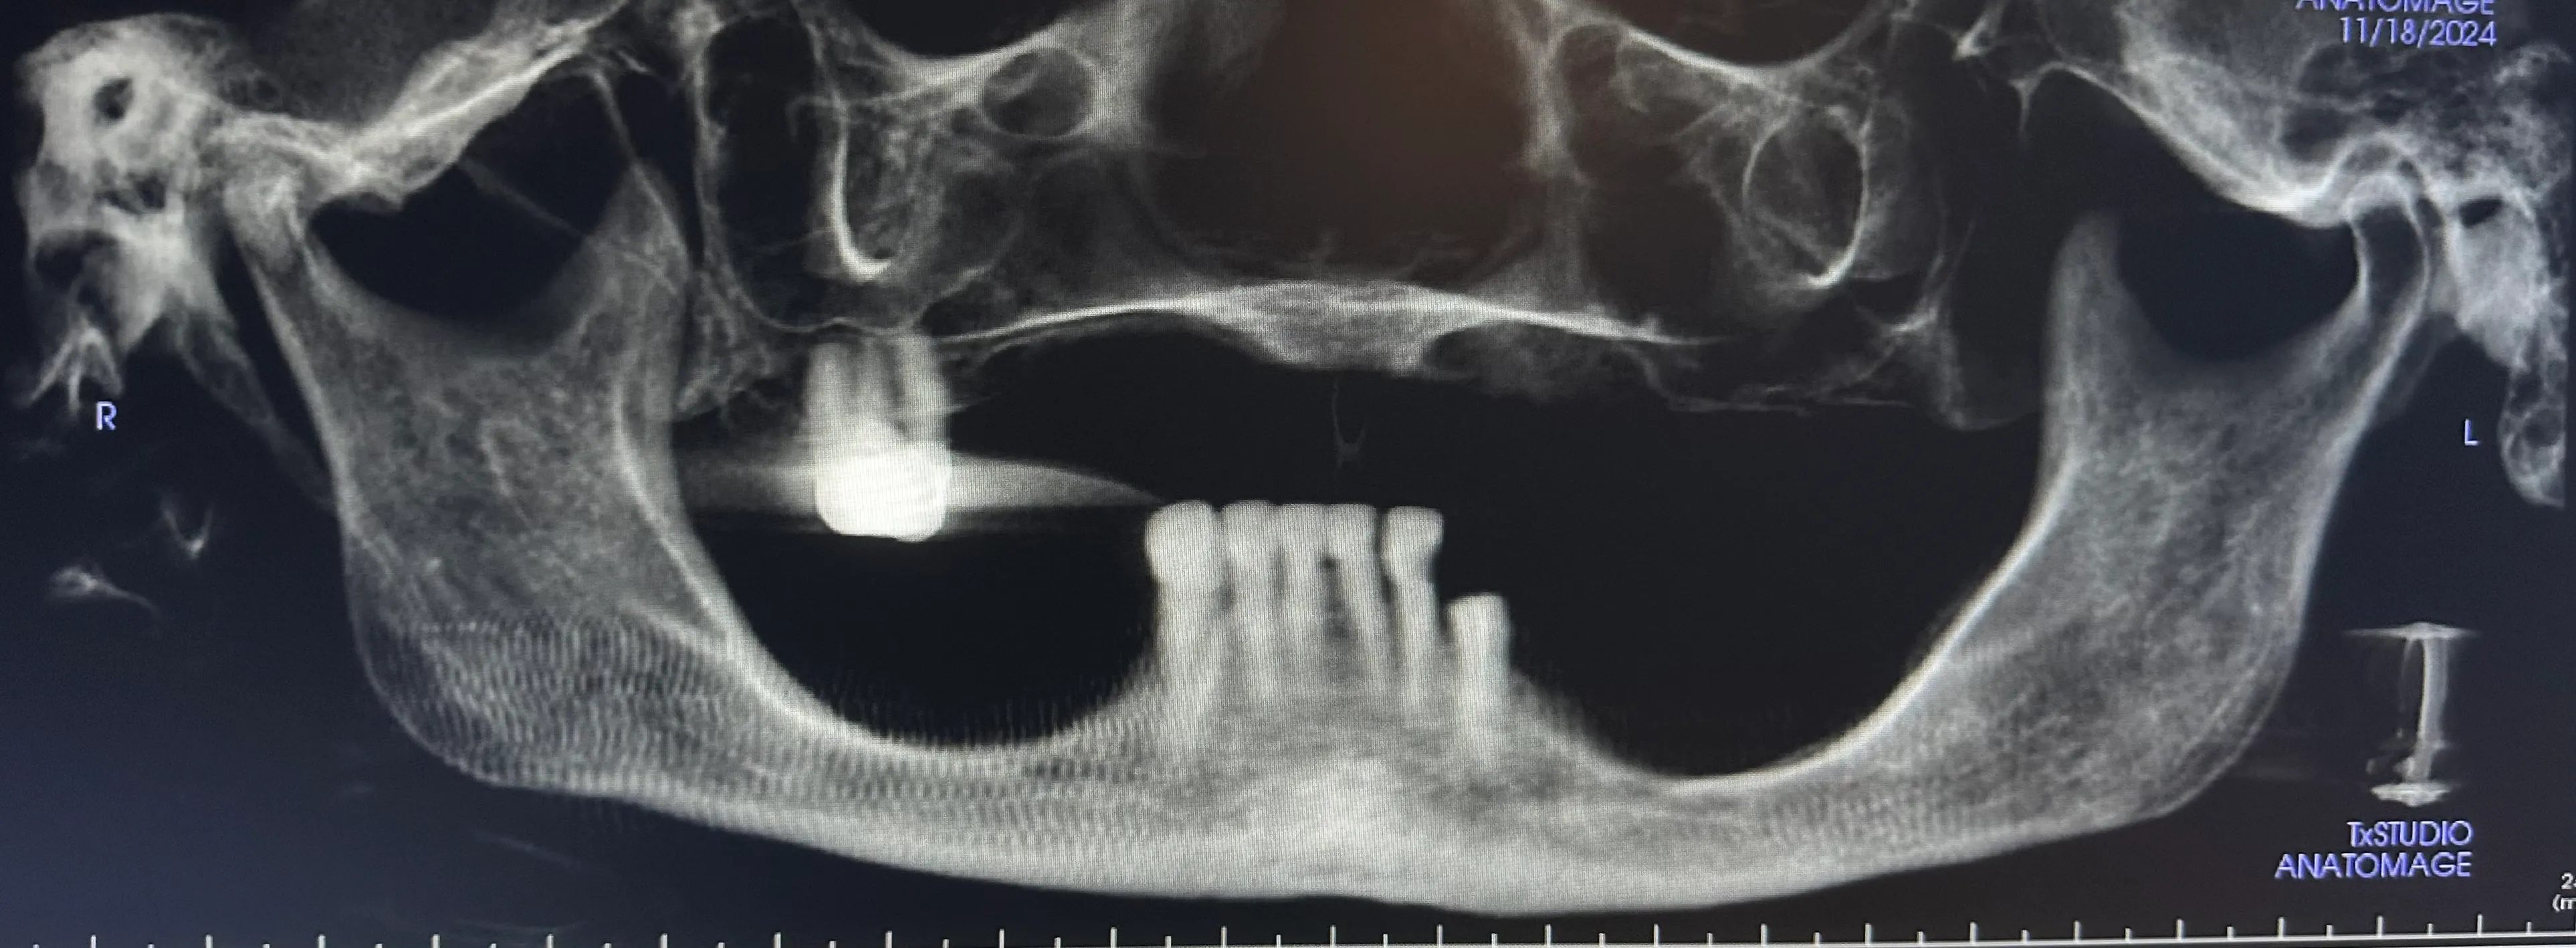

X-ray image of a jaw with dental implants and surgical plates, highlighting the alignment of teeth and orthopedic hardware.

Some patients need only one or two dental implants, while others are completely edentulous (missing all teeth). As with other well-known implant-supported denture options, zygoma implants can support a full arch of prosthetic teeth on just four screws without bone grafting.

Normally, implants are placed in the maxilla to replace missing teeth in the upper jaw. However, some patients have such severe bone loss that there isn’t enough to place an implant safely. In this case, longer implant screws can be used to reach the cheekbones, which are used as an anchor instead.

Without regular stimulation from chewing and biting, jawbone loss (resorption) occurs. We frequently see significant bone loss in patients who have been using dentures for many years. Unfortunately, patients with maxilla resorption are often told that there is no hope for bone grafting or dental implants. However, this is not always the case.